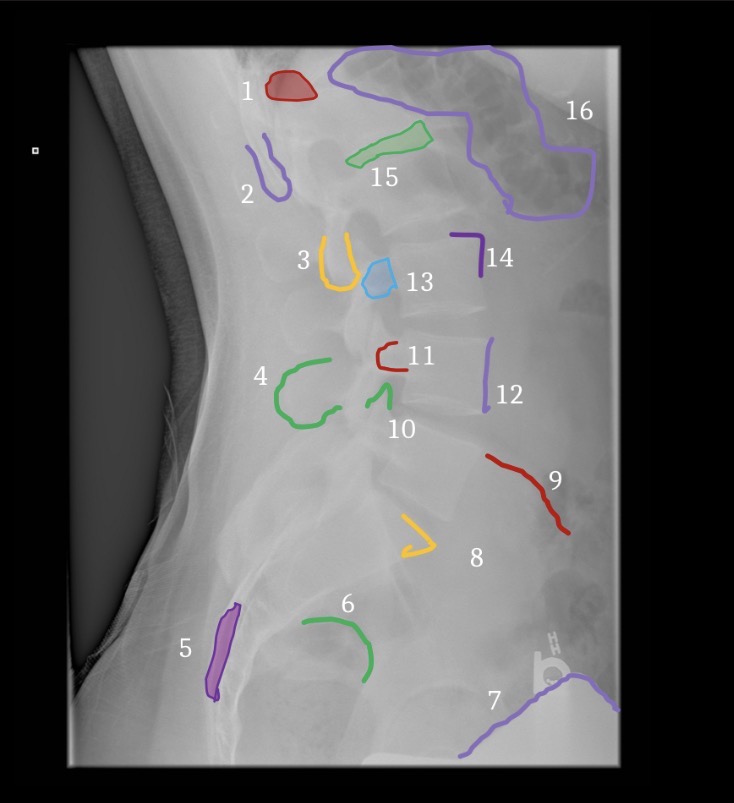

1

Brest

3

Fat deep to abdominal muscle

5

Gluteal crease

6

Lateral margin left psoas muscle

7

Hemidiaphragm

8

Gastric air bubble

4

Inferior articular process

Superior margin of pedicle

Superior articular processes

Vascular channel

Interlaminar space

Lamina

Superior endplate, anterior margin

Superior endplate, posterior margin

9

Accessory tubercle

11

Mammillary Process